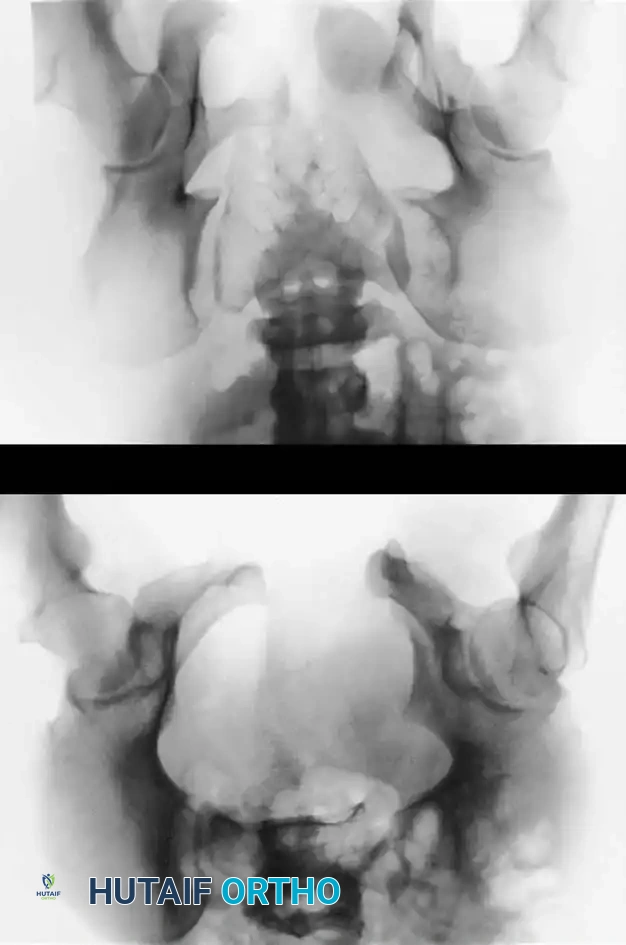

Radiographic Evaluation

Standard evaluation begins with an Anteroposterior (AP) pelvis radiograph. However, definitive surgical planning requires specialized views and advanced imaging.

• Inlet View: Directed 45 degrees caudad. Best evaluates anterior-posterior translation, internal/external rotation, and sacral impaction.

• Outlet View: Directed 45 degrees cephalad. Best evaluates vertical translation and sacral foraminal anatomy.

• CT Scan: The gold standard for evaluating posterior ring injuries, sacral dysmorphism, and preoperative planning for percutaneous fixation.

Image